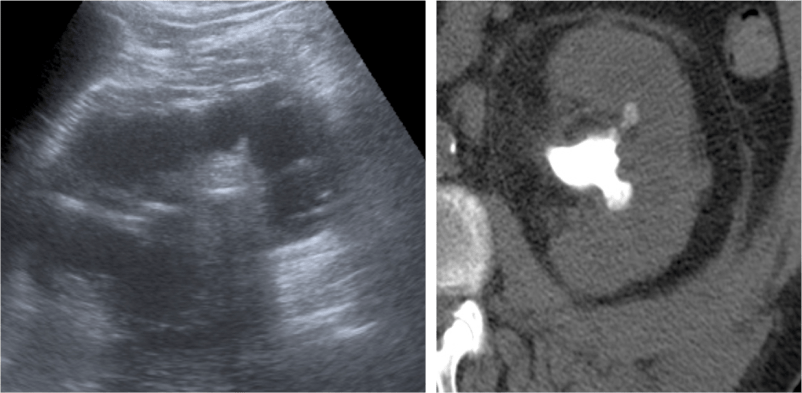

Ecografía:

- Agrandamiento y distorsión de la silueta renal.

- Pérdida difusa de la arquitectura renal normal.

- Gran ecogenicidad central amorfa que corresponde a un cálculo coraliforme en la pelvis renal.

Aunque estos hallazgos son más carácteristicos, se realiza posteriormente una TC para mejor valoración.

Veamos un caso.

Paciente mujer de 62 años que acude por decaimiento general con fiebre y dolor en flanco izquierdo. Ingresa en UVI por signos de sepsis

Nos cuenta antecedentes de pielonefritis e hidronefrosis crónica.

Hallazgos en imagen:

Estos hallazgos pueden ser dificiles de interpretar, ya que una paciente con hidronefrosis crónica y litiasis en el uréter puede haber sufrido una obstrucción que origina un cuadro de dolor en FRI con ruptura de cálices y colección extra axial. Otra probabilidad puede ser un angiomiolipoma que ha roto un aneurisma y ha producido un sangrado. También podríamos estar ante una pionefrosis aunque dada dada la clínica, los antecedentes y al observar los hallazgos en TC podríamos establecer la sospecha de pielonefritis xantunogranulomatosa con alta probabilidad. La confrimación vendrá dada con la nefrostomía y estudio de anatomía patológica.